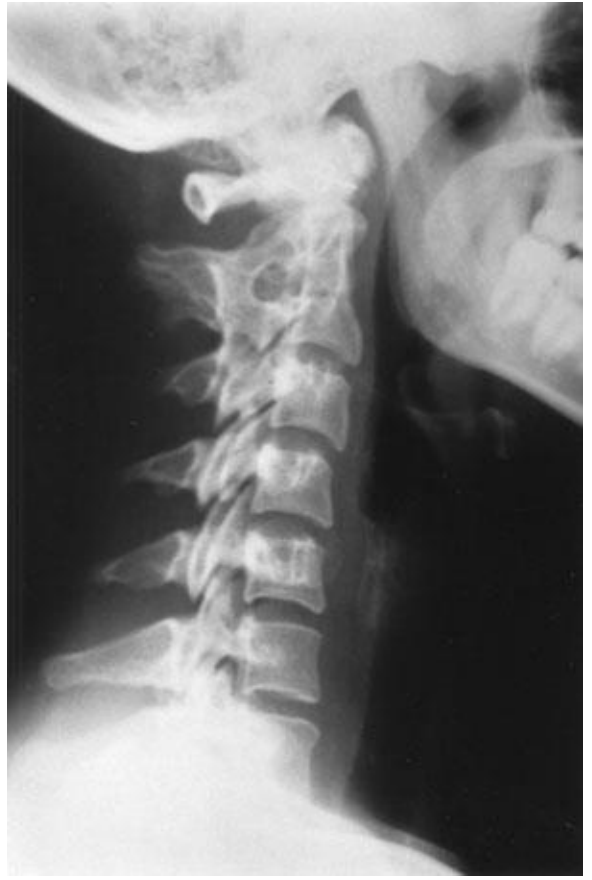

Which type of fusion is this?

What is this?

congenital block vertebra

Q

A

congenital block vertebra C2/C3 with rudimentary disc

C2/C3 congenital block vertebra